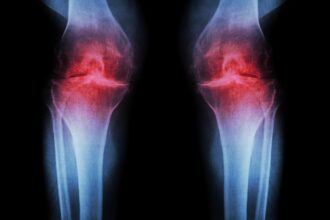

在全球醫療快速變革的今天,健康科技的進步不再只是口號,而是真實地影響醫療品質與疾病存活率。2025 年,多項國際研究與臨床成果持續推動醫療界向前邁進,尤其是在基因治療、人工智慧、疫苗技術、癌症偵測與微創手術領域,皆出現具革命性的突破。本篇將透過權威資料與明確數據,帶你掌握全球醫學界最受矚目的五大健康發展。